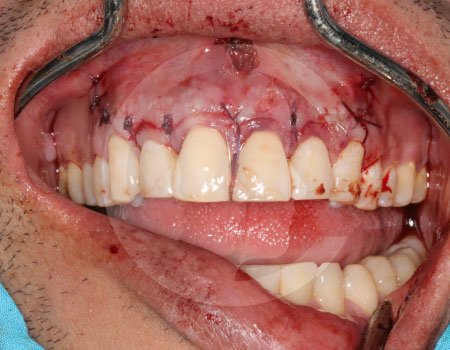

Un absceso es una acumulación de infección que puede causar dolor intenso e inflamación. Cuando el proceso infeccioso no mejora con tratamiento convencional, puede ser necesario realizar un drenaje o manejo quirúrgico.

El tratamiento depende del origen y gravedad de la infección. Puede incluir medicamentos, drenaje quirúrgico o procedimientos específicos para eliminar el foco infeccioso y evitar complicaciones.

En casos de mayor complicación deberá ser ingresado a cuidados hospitalarios, y programar el procedimiento quirúrgico que corresponda